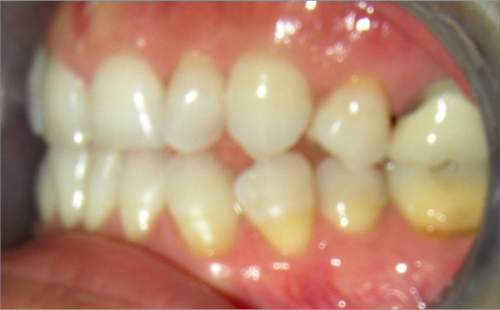

45 year old female:

Diagnosis:

- Missing upper left second bicuspid

- Lower arch crowding

- Edge to edge bite

Treatment:

- Extraction of upper & lower right second bicuspids

- Full fixed appliances

- 21 months